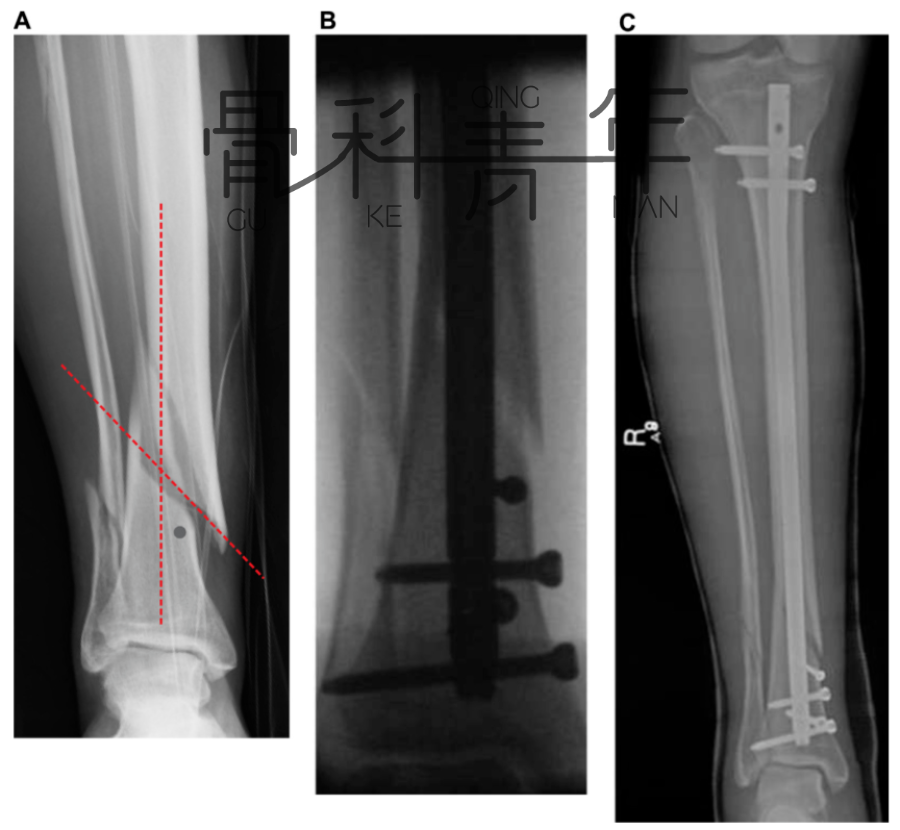

病例示例2:

2a-2c:胫腓骨远端骨折,髓内钉固定,主钉插入及远端锁钉锁定后,可见骨折对线不良,存在移位。

2d-2f:依同法在移位平面拧入螺钉纠正移位,恢复对线后置入阻挡钉维持复位。